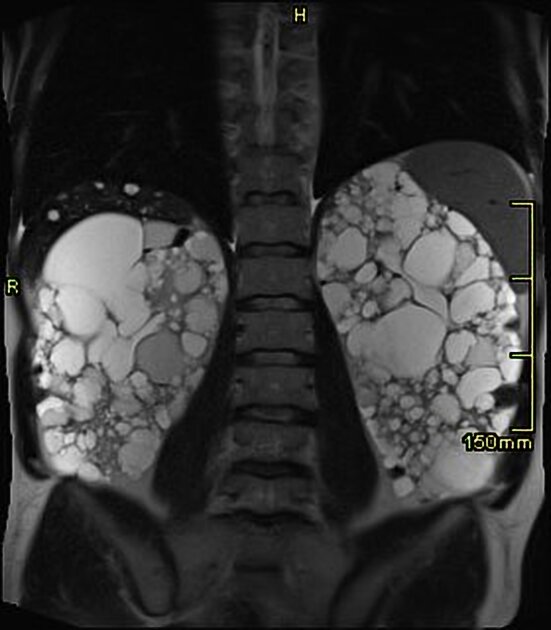

A alta da IRA realmente significa recuperação… ou apenas o começo da DRC futura? Albuminúria, reintrodução de IECA/BRA, iSGLT2 e seguimento precoce podem mudar completamente o prognóstico pós-IRA — e muita gente ainda foca só na creatinina da alta. Esse artigo do Clinical Kidney Journal traz 10 pontos práticos que todo nefrologista deveria revisar no seguimento pós-IRA.